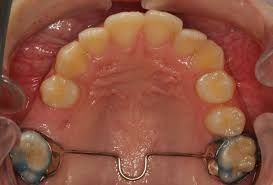

Other types of orthodontic appliances may also be used during the course of treatment. Some of these appliances are removable and can be taken in and out of the mouth, while others will be attached to the teeth until they are no longer needed.

Depending upon the specific needs of the case, these appliances may be used to accomplish a number of things including:

- Widening the jaws to make sufficient space for permanent teeth

- Influencing jaw growth

- The reduction of deep overbites

- Allowing the correction of teeth in crossbite

- Maintaining the space for a permanent tooth when a baby tooth has been prematurely lost

- Minor tooth movement

- Helping to control harmful oral habits